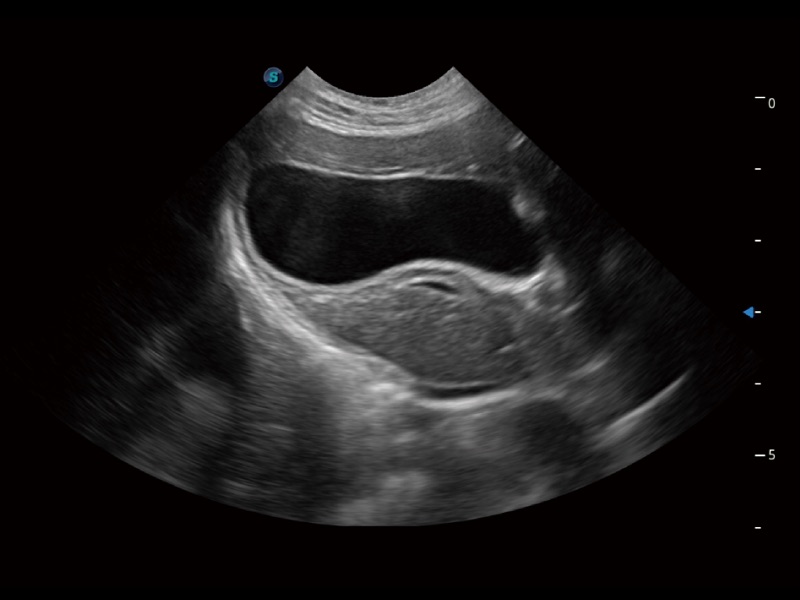

动物是人类最亲密的朋友和最值得信赖的伙伴。db真人体育官网也一直致力于探索动物专用的超声影像解决方案。全新推出的ProPet系列,是db真人体育官网在动物超声影像智能化、专业化、精准化的一次跨越式革新。动物不能用言语来表述自己的不适,通过超声影像,ProPet系列搭建了动物医生与不同物种沟通的“桥梁”,为动物医生注入了“治愈之力”。 ProPet 70将是您值得信赖的超声伙伴。它配备了复合材料线阵探头,帮助动物医生获得卓越精准的临床图像。同时ProPet 70直观便捷的操作体验以及专业的测量工具,可为不同体型和生理结构的动物带来全面临床评估,切实为动物医生提供智能、专业、精准的超声影像解决方案。

ProPet 70 进一步提升了微米成像算法,更加注重对基础原始图像的还原和保留,在有效减少斑点噪声、增强组织边界显示的同时,避免过度优化丟失真实的解剖信息。

ProPet 70专为动物医生设计,对不同的动物体型和生理结构作出了针对性的优化。通过动物影像专用软件,可满足个性化的应用需求,帮助动物医生获得更精确的诊断数据。

ProPet 70 全新的动物超声智能软件和丰富的探头群,为动物医生提供了高清晰度和精细分辨率的图像,无论在宠物、马科、畜牧还是实验室动物等应用中都可以轻松应对,为您的日常工作带来满意的体验。